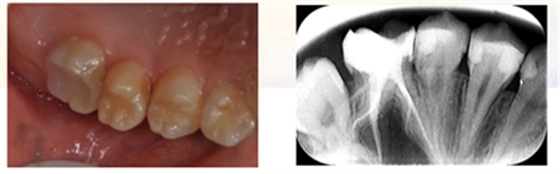

检查:26冠部大面积龋损,仅余近中颊侧残壁,残余牙体颜色变暗,牙龈增生至缺损牙体组织内部,髓腔内炎性牙髓组织增生呈息肉状。探诊(+),冷诊(±),叩诊(-),无松动。

X-ray示:26远中低密度影已穿通髓腔,与近中低密度影几近相连。根尖无低密度影像。

诊断:26慢性牙髓炎